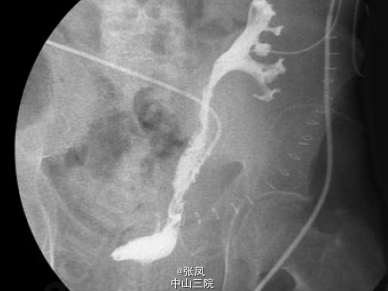

患者术后第12天造影检查提示移植肾输尿管中段部位轻微狭窄,术后20天再次造影检查提示移植肾输尿管明显狭窄并坏死。

患者男,28岁,2009年因头晕、乏力到当地医院就诊,检测发现血肌酐超过1000umol/L,诊断为尿毒症,并开始规律血液透析治疗。2014年在我院行异体肾移植术,手术过程顺利,术中发现移植肾输尿管血供稍差,术后尿量约300ml/h,术后一周后肌酐降至正常,为112umol/L。术后第9天出现尿量减少,约1000ml/d,肌酐升高至145umol/L,考虑排斥反应,给予激素冲击治疗后无明显效果,术后第12天患者出现移植肾周疼痛,压痛明显,为排除尿瘘,行移植肾造影发现移植肾输尿管中段部位轻微狭窄,考虑输尿管狭窄合并少量尿瘘,暂行保守治疗。术后20天移植肾周疼痛加重,并体温升高,无尿,典型的尿瘘症状,再次造影检查提示移植肾输尿管坏死,行紧急手术治疗。